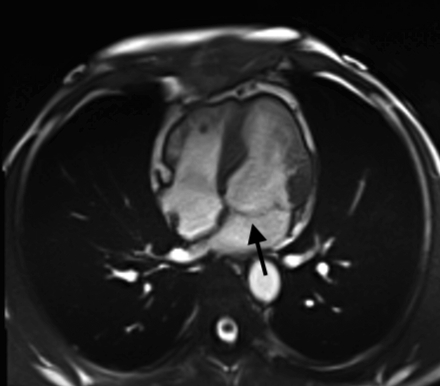

A 51-year-old African American male with history of posterior papillary muscle premature ventricular contractions (PVC), PVC induced cardiomyopathy, and family history of sudden cardiac death in his mother who presented to the emergency department due to palpitations. Electrocardiogram (ECG) showed sustained monomorphic VT at a rate of 160 bpm. This converted to normal sinus rhythm with intravenous amiodarone and metoprolol. Further work up included cardiac magnetic resonance which identified a 4 x 1.8 x 1.4 cm SMA on the basal inferior and inferolateral walls. There was near transmural late gadolinium enhancement (LGE) of the aneurysm and an associated 7 mm of MAD with posterior mitral valve prolapse (MVP). He underwent left heart catheterization which was normal. ECG showed a superior right axis with associated right bundle branch block which correlated to a basal inferolateral exit and to the location of the SMA. Ultimately the patient underwent implantation of secondary prevention implantable cardioverter-defibrillator and initiation of sotalol.